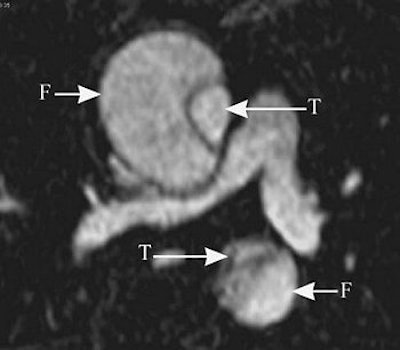

The series of images illustrate the typical manifestations of aortic dissection, including Stanford A (top image, both VR; second image, axial MPR) and Stanford B (third image, arterial phase VR, venous phase VR; fourth image, MIP and VR; fifth image, axial MPR). T = true lumen. F = false lumen. Black arrowhead = entry site. All images courtesy of Qi Liu, Ph.D.